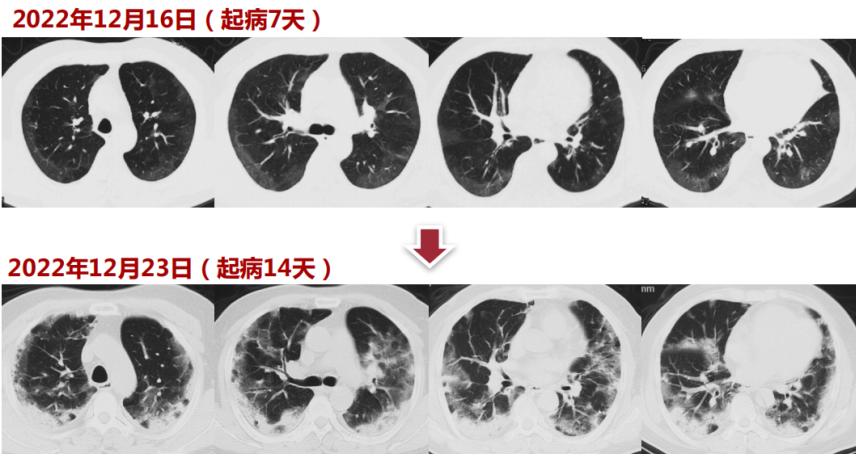

患者,男性,73岁,主诉:发热10天,呼吸困难5天。入院时间:2022年12月25日。10天前患者因接触新冠感染家属后出现发热,伴咳嗽,无痰,体温最高38.4℃,自服布洛芬后体温可下降,但仍反复,体温波动于37.8~38.3℃。5天前于静息状态下感呼吸困难,咳嗽、咳黄痰,未用药,症状持续不缓解。3天前至当地医院就诊,完善胸部CT示“肺部感染”。2天前,测指脉氧饱和度70%左右,收入望京医院ICU病房,住院期间予“莫西沙星、糖皮质激素”治疗后症状无缓解,经120转入我院继续治疗。外院胸部CT可见右肺上叶有一较大空腔,右肺上叶胸膜下有一不规则结节,双肺弥漫磨玻璃影,下肺和胸膜下为著。既往史、个人史及家族史

胸部CT可见右肺上叶肺大泡、不规则结节,双肺弥漫磨玻璃影。初始治疗方案

入院15天前(12月9日)出现发热,T 39℃,伴畏寒、咳嗽、咳痰、呼吸困难,自服布洛芬、阿莫西林等。入院8天前(12月16日)呼吸困难加重,伴高热(体温39℃),指氧饱和度80%(未吸氧),新冠核酸(+),血常规(12月21日):WBC 9.04×109/L,LYM 1.01×109/L,CRP 156 mg/L,PCT<0.072 ng/ml;胸部CT考虑新冠肺炎。血气分析(12月21日,吸氧条件不详):pH 7.48,PaCO2 29 mmHg,PaO2 56 mmHg,HCO3- 21.6 mmol/L,Lac 2.3 mmol/L。当地给予吸氧、激素、抗生素治疗(具体不详)。第二阶段(转入我院急诊)

1天前因胸部CT(12月23日)加重转入我院急诊。新冠核酸(12月24日,阳性)。血常规(12月24日):WBC 10.77×109/L,NEU 10.28×109/L, LYM 0.37×109/L,CRP>200 mg/L,PCT 0.18 ng/ml。血气分析(12月24日,面罩15 L/min):pH 7.47,PaCO2 32 mmHg,PaO2 71 mmHg,HCO3- 25 mmol/L,Lac 1.0 mmol/L。凝血(12月24日):D-D 6.88 mg/L,FDP 23.14 μg/ml。HFNC+化痰+莫西沙星治疗1天后转入呼吸科。起病后精神、食欲、睡眠欠佳,二便正常。胸部CT:起病7天,患者双肺胸膜下可见浅淡磨玻璃影;起病14天,胸膜下可见实变影伴周围磨玻璃影,病变范围较前扩大。2型糖尿病1年,不规律服用卡格列净1片(早餐前),二甲双胍缓释片0.5 g(午餐及晚餐前),空腹血糖约7 mmol/L。否认高血压、冠心病、脑血管病病史;否认肝炎、结核等病史;否认手术、外伤、输血史;否认食物、药物过敏史;无吸烟史,无酗酒;适龄婚育,家族史无特殊。T 37.2℃,HR 93 bpm,RR 23 bpm,BP 116/55 mmHg,SpO2 93%(HFNC FiO2 1.0,45 L/min)。神清,精神差,查体欠配合。双肺呼吸音清,双下肺可闻及湿啰音;心界无明显扩大,心律齐,各心脏瓣膜区未闻及杂音;腹软,无压痛、反跳痛及肌紧张,肠鸣音4次/min;双下肢无凹陷性水肿。新型冠状病毒肺炎(危重型),Ⅰ型呼吸衰竭,2型糖尿病。初始治疗